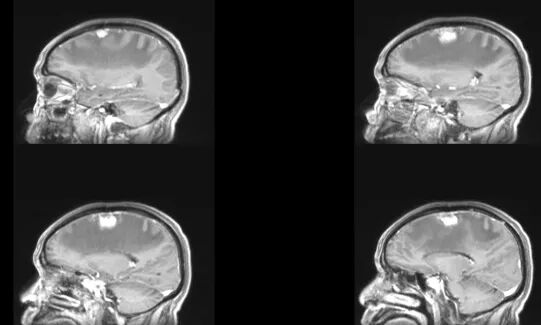

李大伯因左側(cè)肢體乏力4天到惠州三院神經(jīng)醫(yī)學中心門診就診,CT檢查提示:右側(cè)額頂葉腦水腫查因:腦腫瘤?隨后,李大伯入住神經(jīng)外科二病區(qū),醫(yī)生進一步完善檢查后發(fā)現(xiàn),李大伯患上右側(cè)額葉占位性病變!經(jīng)過手術(shù)治療后,李大伯情況好轉(zhuǎn),病理診斷是轉(zhuǎn)移瘤!